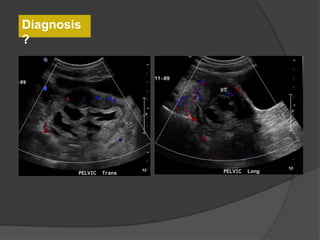

Follow-up US

Diagnosis

?

Case 2: 12 year old female with abdominal pain

Dilated fallopian tube with thickened and enhancing tubal wall

Right

ovary

Complex

tubular

mass

Normal left ovaryNormal left ovary flow

Diagnosis: Torsion of the left Fallopian tube

Dilated tube with thickened, echogenic walls

and absence of vascular flow in the tube